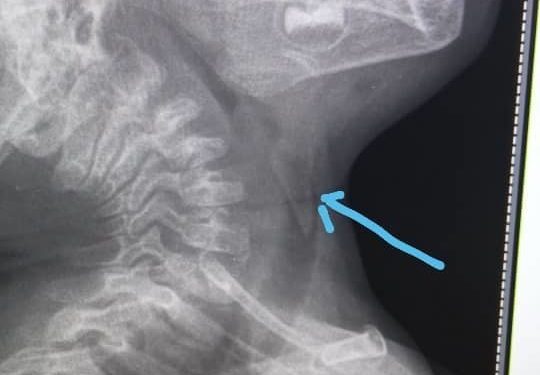

«2 жаштагы баланы түшкө маал алып келишти. Кекиртегине сөөк тыгылып калып, дем алуусу кыйындап жаткан экен. Аны учурунда албасак, чарчап калмак. Алынган сөөктүн узундугу 2 сантиметр экен»,— деди оорукананын дарыгери Элмурат Эркулов.